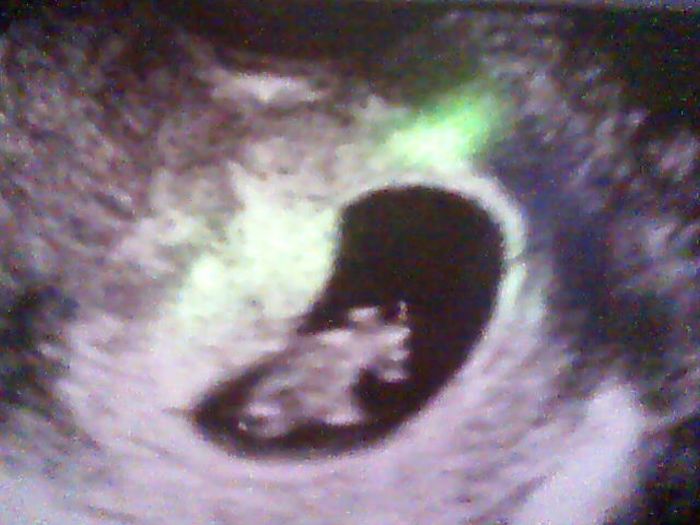

Holky tak jsem zpět od doktora....tak naštěstí je vše v pořádku,v děloze není vidět žádný náznak krvácení nebo něčeho co by nemělo být v pořádku,tak mi rovnou udělal i kontrolu...takže mám počítat těhu podle poslední ms a to je že si musím změnit mětřík,jsem už 8+1 i když na ultrazvuku jsem o dva dny méně říkal,že to necháme podle ms...prdolka pěkně porostl minlé pondělí měl 6mm a dneska už 15,35mm...už jdou vidět i náznaky rukou a nohou ma fotce co jsem dám je hlavou dolů....další kontrolu mi doktor posunul o týden dříve tj 14.4 kde mi už vezmou krev na screening a zároven se mrkne na šíjové projasnění....Marcy já porodila prvního syna a bylo mi 25 let....ono to jednou výjde,.moc ti budu držet palečky

Veverusko, super krásná fotecka a krásné zprávičky

Veve, moc krásná fotka. Jsem opravdu ráda, že "prďolka" hezky roste